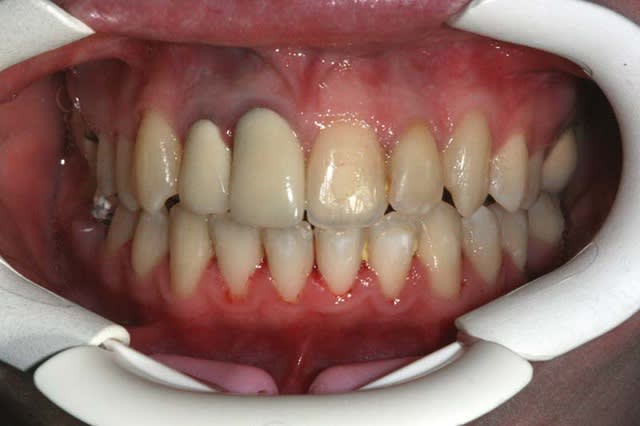

pour les impatients, voici la photo du cas, fin de TTT., prise il y a 1 an

Les milieux sont décalés, la 13 et la 24 apparaîssent trop vestibulées... je doute fort que l'occlusion soit bien équilibrée.

C'est vraiment ta fin de traitement ?

Phil.

"""Les milieux sont décalés,"""

Evidemment que les milieux sont décalé (eh patate !)

comme il est prévu de refaire les centrales, je ne vais pas tenir compte d’une dent prothétique plus étroite que la dent naturelle proximale, sinon ce seront les nouvelles dents, toutes neuves qui seront décalées par rapport au bas

ça commence bien ;-)))